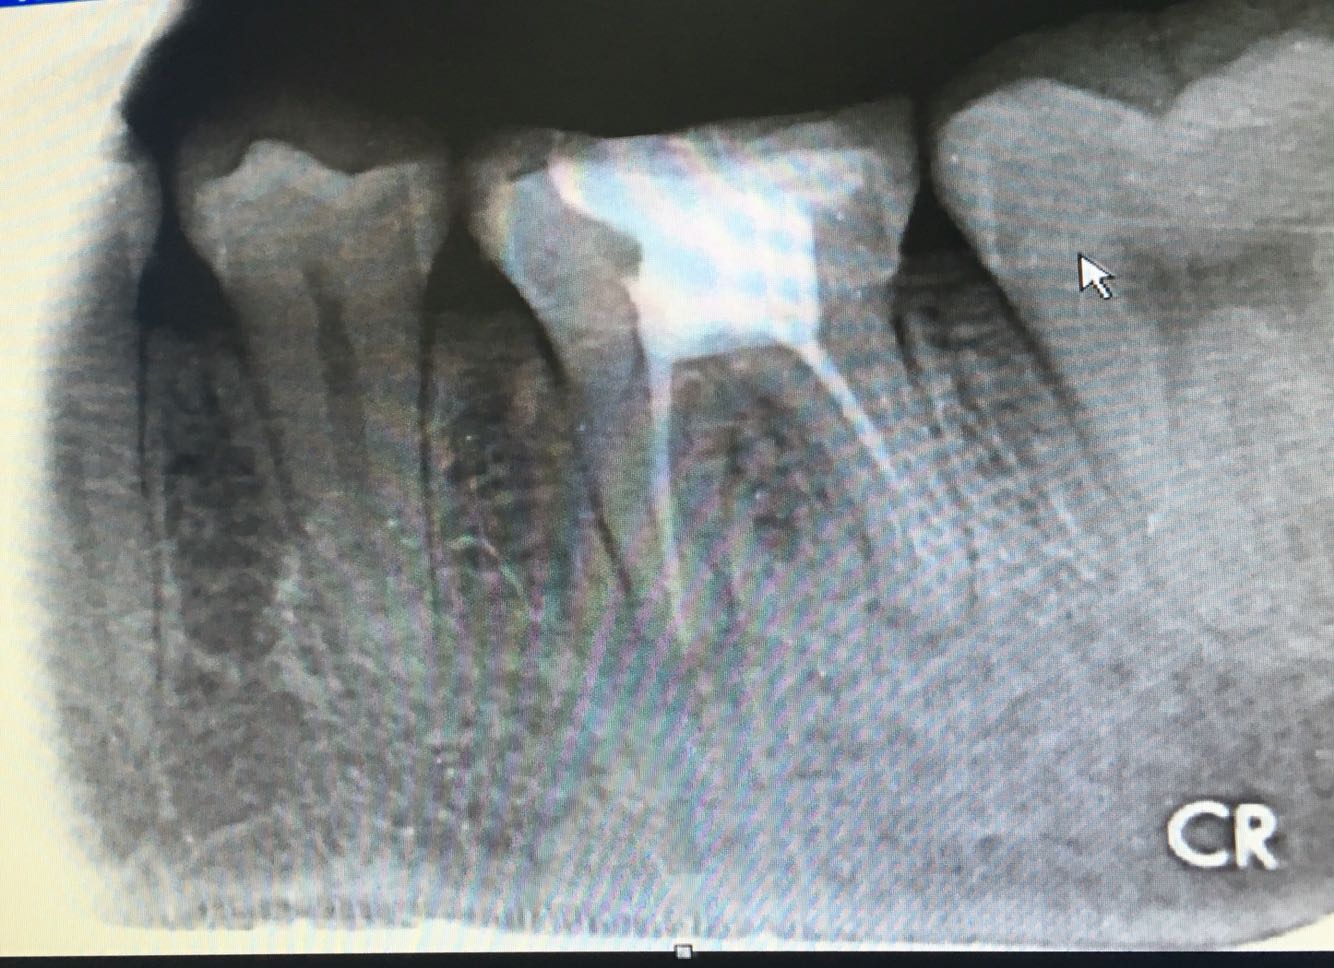

检查:26冠部大面积白色补料,远中轴角处牙体活动撕裂,齐龈,松iii度,剩余牙体组织不松,探痛(-) ,冷水反应(-) ,叩诊无不适,牙齿无松动,牙 龈无充血水肿。X-ray 示:26冠部充填高密度影像,近中遗漏一根管,远中根尖欠填。

诊断:26冠折,26慢性牙髓炎 (欠填) 治疗计划:26拔除松动残片,26根管再治疗术.术后高嵌体修复  处置: 26局麻下拔除松动残片,去除原表面暂充填物,丁克除去除远中根管内牙胶尖,疏通根管,电测根长,17mm,.近颊根管疏通,电测17.5mm,EDTA扩大至30#,3%双氧水+0.9% 生理盐水交替冲洗,拭干,根管糊剂+牙胶尖冷侧压法根充,氧化锌粘固粉暂 封。X-ray 示:26根充完好。建议1周后无症状高嵌体修复,常规医嘱。

患牙两年前根管治疗,远中根欠充,近颊根管遗漏,根尖片示根尖区无异常,牙体叩痛无,但是想要进行修复治疗牙体治疗必须完善了,所以与患者沟通,此牙进行根管再治疗,观察两周后进行修复术